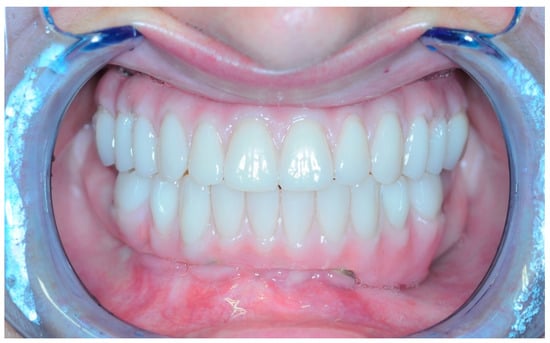

3.5. Function and Aesthetics